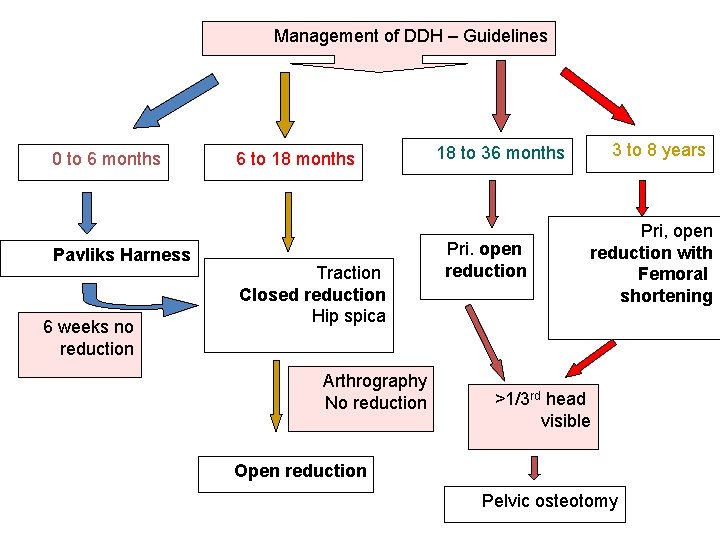

Developmental Dysplasia Of The Hip DDH Definition Dysplasia

Developmental Dysplasia Of The Hip DDH Definition Dysplasia

Developmental Dysplasia Of The Hip DDH Definition Dysplasia

Developmental Dysplasia Of The Hip DDH Definition Dysplasia

Developmental Dysplasia Of The Hip DDH Definition Dysplasia

Developmental Dysplasia Of The Hip DDH Definition Dysplasia

Developmental Dysplasia Of The Hip DDH Definition Dysplasia

Developmental Dysplasia Of The Hip DDH Definition Dysplasia